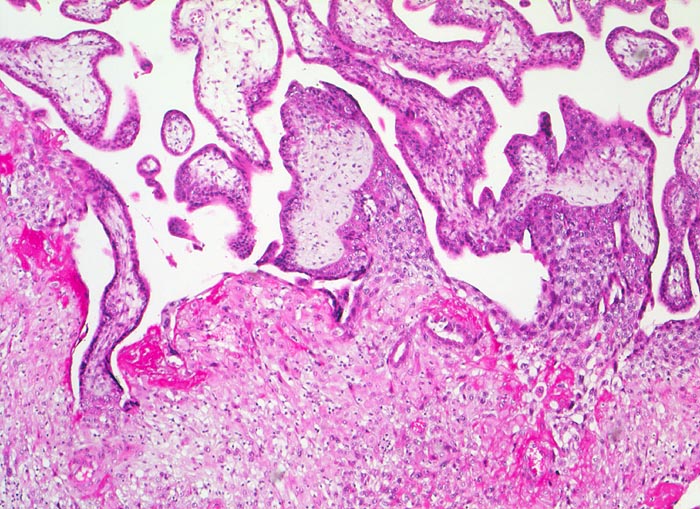

Morphologie:

• Plazenta accreta: Plazentarzotten haften dem Myometrium an ohne deziduale Zwischenschicht. Fibrin und Trophoblast kann vorhanden sein.

• Plazenta increta: Plazentaimplantation innerhalb des Myometriums.

• Plazenta percreta: Penetration der Plazentarzotten durch die gesamte Dicke des Myometriums hindurch.